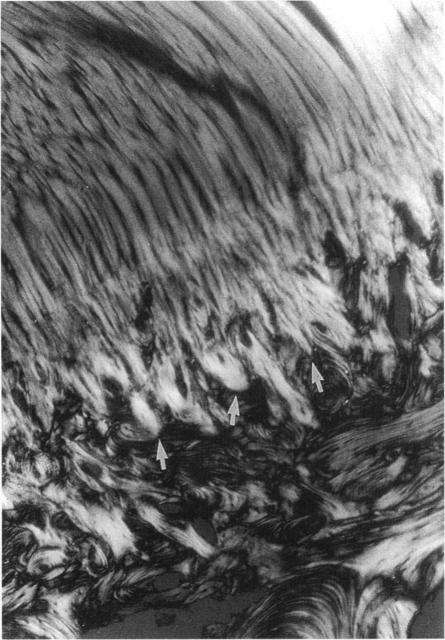

At chondral ligament insertions the calcified fibrocartilage interdigitates deeply with the lamellar bone. The shape of this interface is formed under physiological loading conditions. For the purpose of morphological comparison between different ligament entheses in the rabbit knee, the number and frequency of interdigitations and thickness of calcified fibrocartilage were quantitated at the femoral insertion of the medial collateral ligament, both insertions of the cruciate ligaments, and the tibial insertion of the patellar ligament. Among the insertions, the femoral insertion of the medial collateral ligament showed the lowest frequency and depth of interdigitations at the soft tissue-bone interface, but had the thickest zone of calcified fibrocartilage. An inverse relationship was found at the insertion interface of the cruciate and patellar ligaments. The frequency and depth of interdigations at the bone-soft tissue interface at different chondral entheses seem to be related to the mechanical strength of the respective ligament; meanwhile it may be hypothesised that the thickness of the calcified fibrocartilage might be more related to the amount of motion which takes place at an insertion.

在软骨韧带附着处,钙化纤维软骨与板层骨深度交错。该界面的形状是在生理负荷条件下形成的。为了对兔膝关节不同韧带附着点进行形态学比较,对内侧副韧带股骨附着点、交叉韧带的两个附着点以及髌韧带胫骨附着点的交错数量和频率以及钙化纤维软骨的厚度进行了定量分析。在这些附着点中,内侧副韧带股骨附着点在软组织 - 骨界面处的交错频率和深度最低,但钙化纤维软骨带最厚。在交叉韧带和髌韧带的附着界面发现了相反的关系。不同软骨附着点处骨 - 软组织界面的交错频率和深度似乎与相应韧带的机械强度有关;同时可以推测,钙化纤维软骨的厚度可能与附着点处发生的运动量更相关。